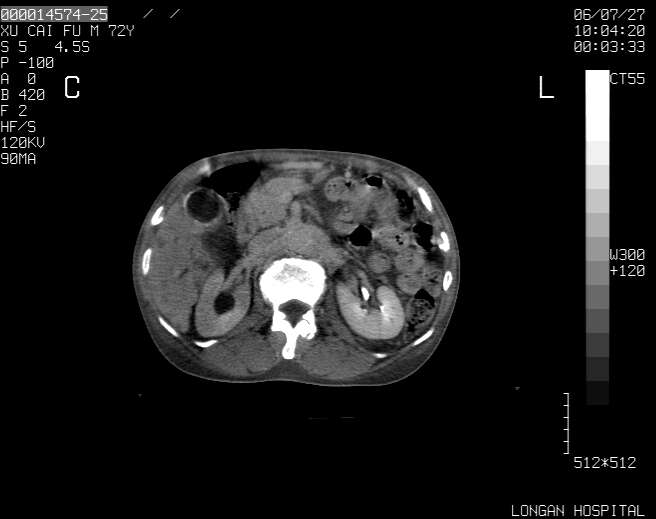

以下是引用winter在2006-7-30 20:14:00的发言:[br]1、考虑胆囊癌伴胆道侵犯并高位胆道梗阻、肝内多发转移、腹膜后淋巴结转移。[br]2、右肾轻度积水。[br]3、老人家72岁了胰腺头体尾部均较饱满,不过未见密度异常及其他异常征象。[br]4、腹水。

以下是引用jiajie在2006-7-31 7:10:00的发言:[br]考虑肝转移瘤,腹膜后淋巴结增大。[br]胃癌不能除外,建议胃镜检查。